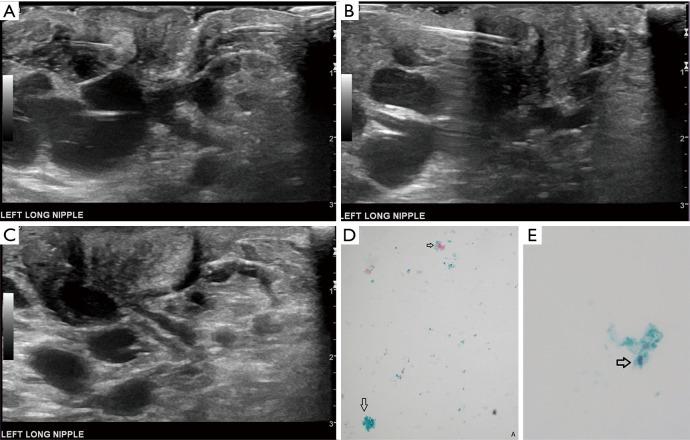

A 34-year-old lactating female presented with a 3-month history of worsening left breast and nipple pain radiating to the left upper outer quadrant, not relieved with conservative therapies. The physical exam revealed a small indentation and a small palpable nodule of the left nipple. There was no associated erythema or redness. Targeted ultrasound and subareolar magnification views revealed findings most consistent with a probably benign inspissated clogged milk duct. Given the patient's history, inability to express milk from the left breast, and plan to lactate for another year, ultrasound-guided aspiration was desired. Post-aspiration images demonstrated complete resolution of the nipple mass. Pathology revealed blood and proteinaceous material, in keeping with the diagnosis of inspissated clogged milk duct. Following the procedure, the patient's symptoms resolved completely.

一名34岁的哺乳期女性,左乳房和乳头疼痛加剧3个月,疼痛放射至左乳房外上象限,保守治疗未能缓解。体格检查发现左乳头有一个小凹陷和一个可触及的小结节。无相关红斑或发红。针对性超声检查和乳晕下放大视图显示的结果最符合可能为良性的浓缩性乳腺管堵塞。鉴于患者的病史、左乳房无法挤出乳汁以及计划再哺乳一年,希望进行超声引导下抽吸。抽吸后的图像显示乳头肿块完全消失。病理检查显示为血液和蛋白质物质,符合浓缩性乳腺管堵塞的诊断。手术后,患者症状完全缓解。